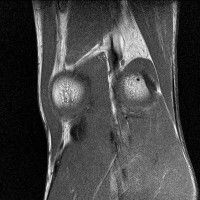

무릎 mri 간단히 봐주실 수 있으시나요 ㅠㅠ

안녕하세요 8년전 십자인대 수술하고 최근 무리한 운동에 무릎 불편감이 생겨서

mri 찍었습니다.

진단결과는 첫 찍은 병원에서 활액막염 이라는 진단을 받았습니다. 혹시 봐주실 수 있으실까요?

올라온 MRI가 단편적이라서 정확한 진단에 어려움이 있지만 십자인대에는 큰 이상이 있지는 않은것 같으며, 무릎관절내 물이 있는 것으로 보아 활액막염의 진단이 맞을 것 같습니다.

하지만 단편적인 영상이기 때문에 촬영병원에서 정확한 판독지 등을 받으시는 것이 좋겠습니다.